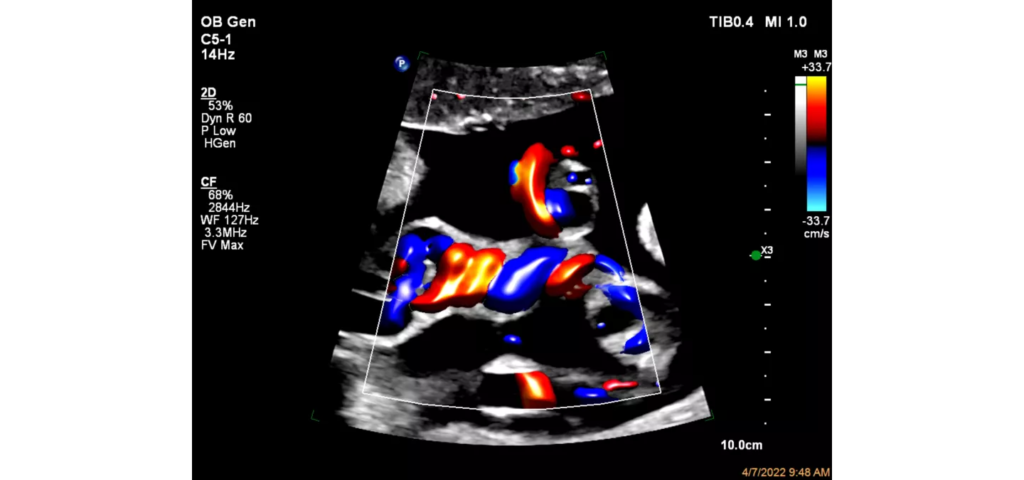

Philips EPIQ Elite ultrasound features an exceptional level of clinical performance, workflow, and advanced intelligence to meet the challenges of today’s most demanding practices. The EPIQ Elite platform brings ultimate solutions to ultrasound, with clinically tailored tools designed to elevate diagnostic confidence to new levels.